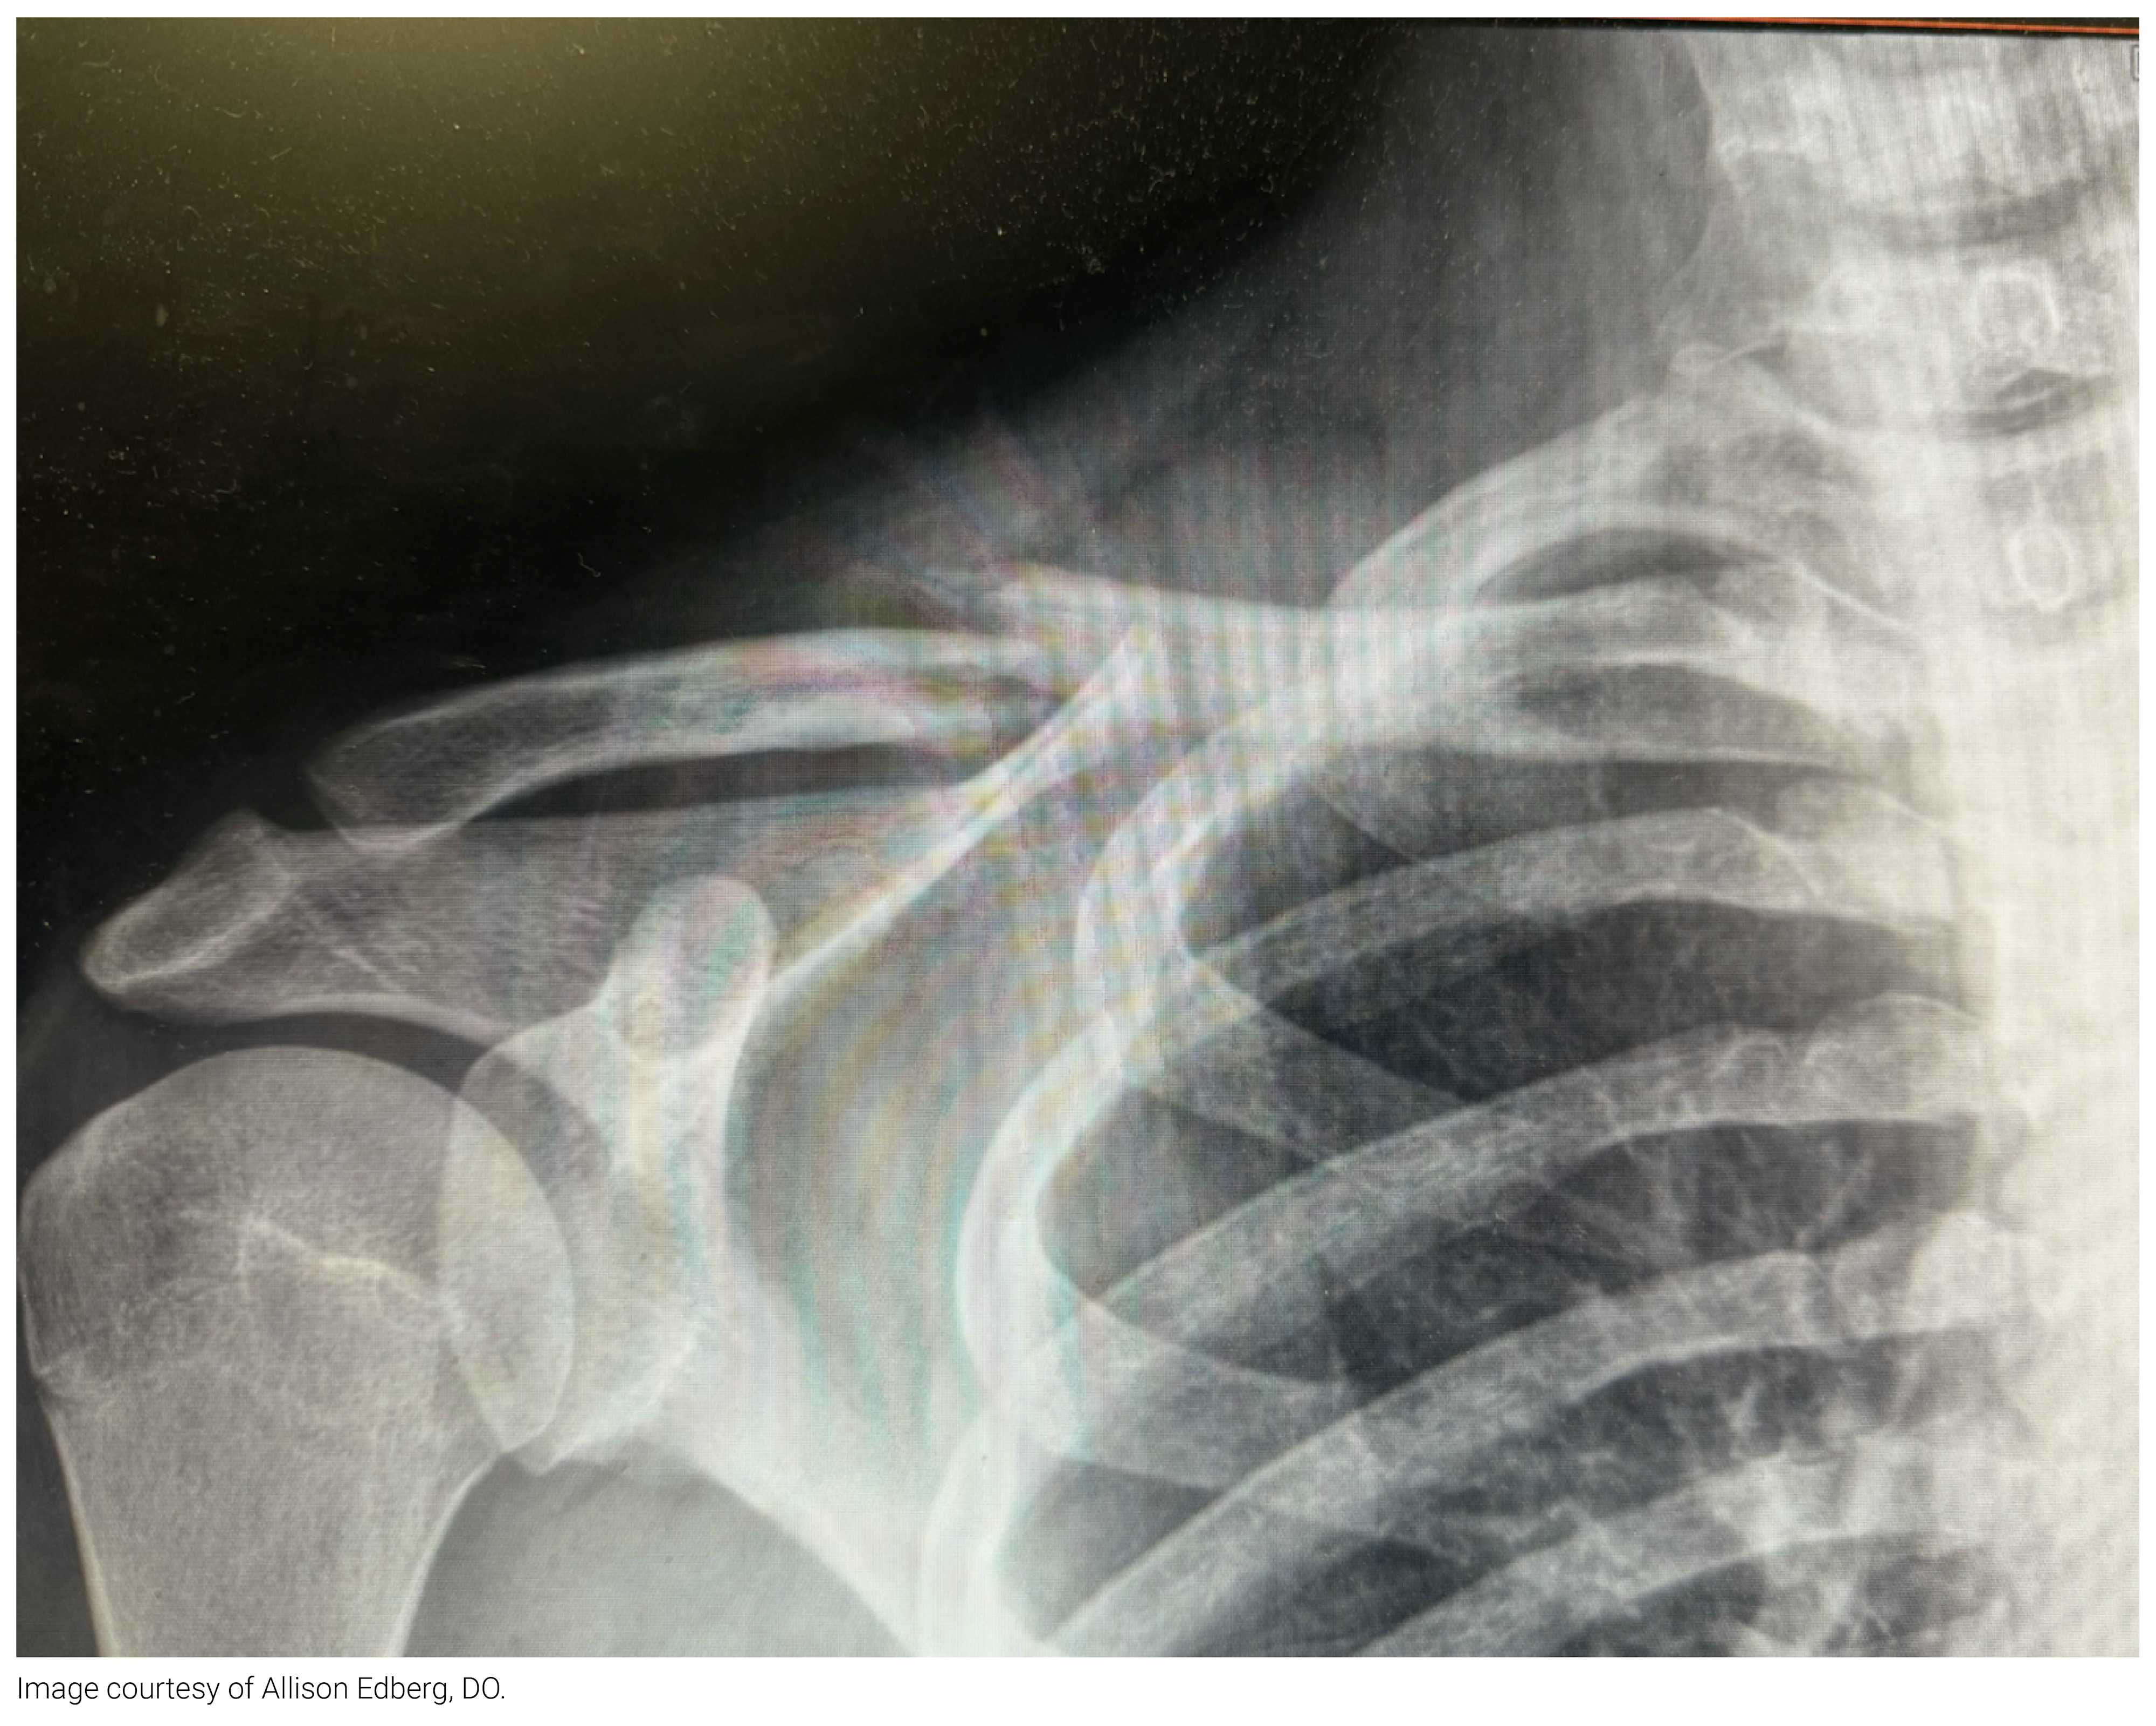

Fracture of which of the following structures should prompt a high index of suspicion for high-energy trauma?

Scapula Fx

A 34-year-old man presents to the ED after he was struck by a motor vehicle while on his bicycle. He landed on his right side and reports pain to the right shoulder. On exam, there are no abnormalities, including on dermatologic and neurovascular assessment. His shoulder X-ray is shown above. What is the treatment for this injury?

A 12-year-old girl presents to the ED after her cat bit her hand. The cat is fully vaccinated. There are two small puncture wounds to the hypothenar eminence. No foreign bodies are identified on X-ray or visual inspection of the wound. The patient has had an allergic urticarial reaction to penicillin in the past. Which of the following is the best prophylactic treatment?